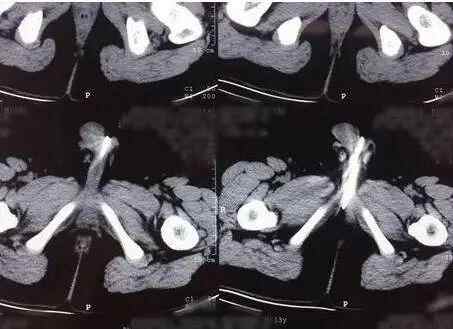

据扬州大学附属医院儿外科主治医师邱宇介绍,当时医生就判断孩子可能尿道中有结石或者异物。在进一步问询中,这名男孩支支吾吾不太肯配合,于是医生便通过泌尿系统B超进行进一步检查。“当时吓了一跳,在尿道后部发现了一串的珠子。”

邱宇告诉记者,对孩子进一步问询后,男孩道出了实情,原来他在一个多星期前,将家中20多颗磁力珠玩具塞进了尿道。

湖南省儿童医院泌尿外科曾收治一名尿急、尿痛、尿失禁症状的男孩。经过手术,医生从男孩尿道及膀胱内,共取出68颗磁力珠。